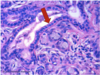

Submandibular Gland

* Both serous and mucous cells.

* Serous cells form serous demilune capping mucous acini.

* Myoepithelial cells surround acini.